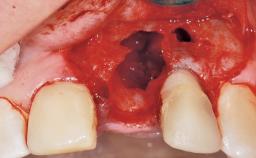

Immediate Flapless Placement of an Implant in a Maxillary Left Central Incisor Site

A 42-year-old female patient was referred to our clinic at the School of Dentistry of the University of São Paulo in November 2004, presenting a deficient restoration in the upper left central incisor. The clinical examination revealed no gingival retraction or any signs of gingival inflammation and, therefore, previous periodontal treatment was not considered. The patient presented a high lip line at full smile and a thin tissue biotype. This combination characterized a high-risk situation from an anatomic point of view, which required careful preoperative planning and cautious surgical execution.

Soft Tissue Anatomy Intact Defective

Bone Volume Horizontally and vertically sufficient Horizontally deficient Deficient vertically or deficient vertically AND horizontally

Socket Integrity Sufficient, with intact bone walls

Bone Volume Sufficient, with intact walls